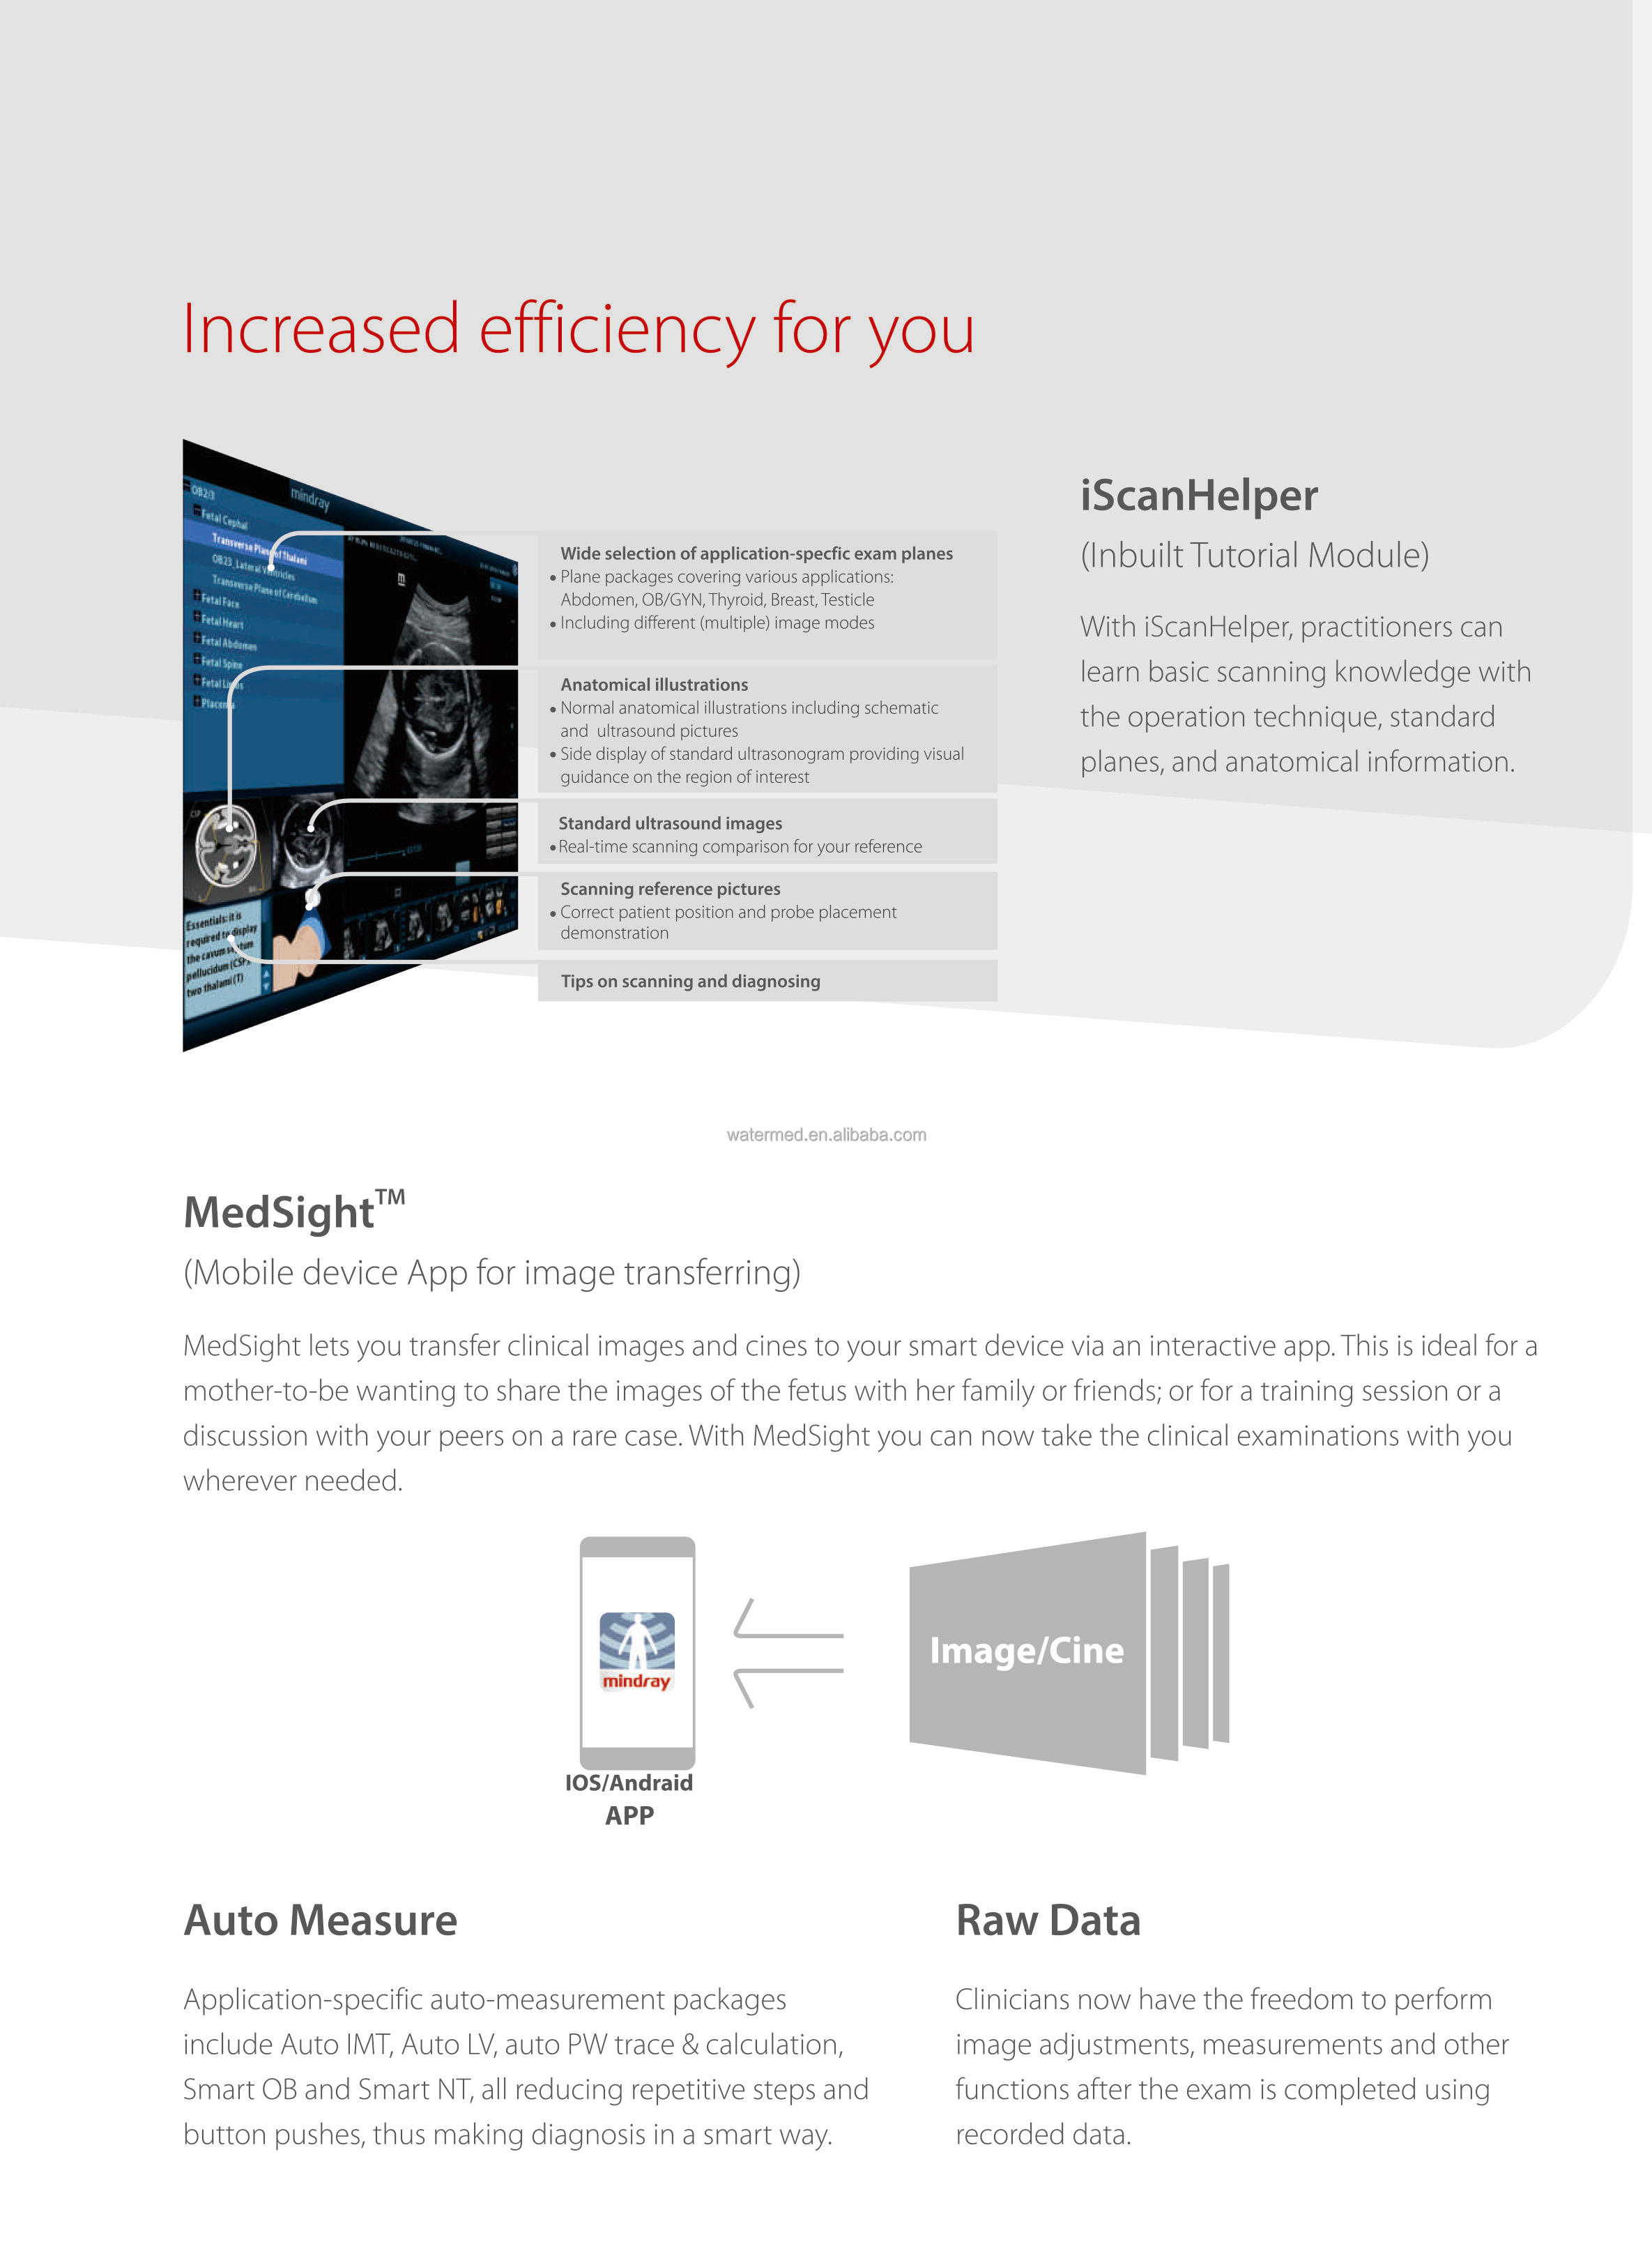

Product Description

Available Mindray 4D Ultrasound DC-40 Mindray Cart

feature

Tissue Harmonic Imaging: Yes

Spatial compounding (=CrossXbeam): Yes (iBeam)

Speckle Reduction (=SRI): Yes (iClear)

Automatic Image Selection (B Mode): Yes (iTouch)

Automatic Image Selection (Doppler): No

Write Zoom: Yes (iZoom)

Triple Mode: Yes

Needle Enhancement or Needle Identification: Yes (iNeedle)

Automatic NT measurement (=Sono NT): Yes (Smart NT)

Automatic Follicle 2D Measurement: No

Automatic Hair Follicle 3D Measurement: No

Automatic IMT: Yes

- Auto IMT (Real Time): No

Automatic B/M/D Measurement: No

Automated LH measurement (Automatic Functional Imaging (AFI), Cardiac Motion Quantification (CMQ) or Automated EF (Ejection Fraction): Yes

Real-time dual (B/BC) mode: Yes

SmartExam or Scan Assistant: Yes (iWorks)

Fusion: no

Raw data files: yes

Flexible reporting: yes

Barcode Reader: Yes

Gel warmer: yes